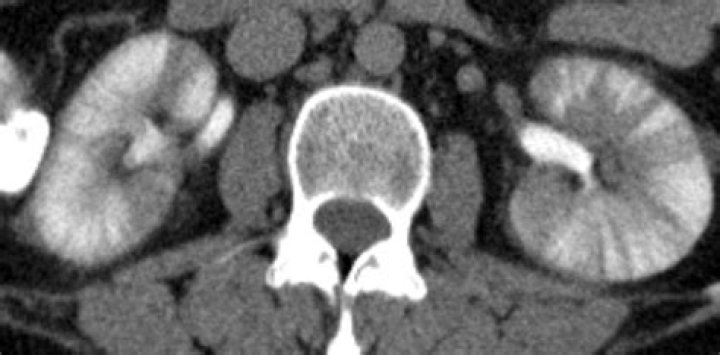

Striated nephrogram is a descriptive term indicating an appearance of alternating linear bands of high and low attenuation in a radial pattern extending through the corticomedullary layers of the kidney on iodine-based intravenous contrast enhanced imaging.